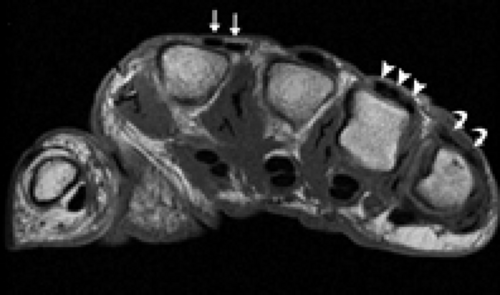

MRI OF THE HAND